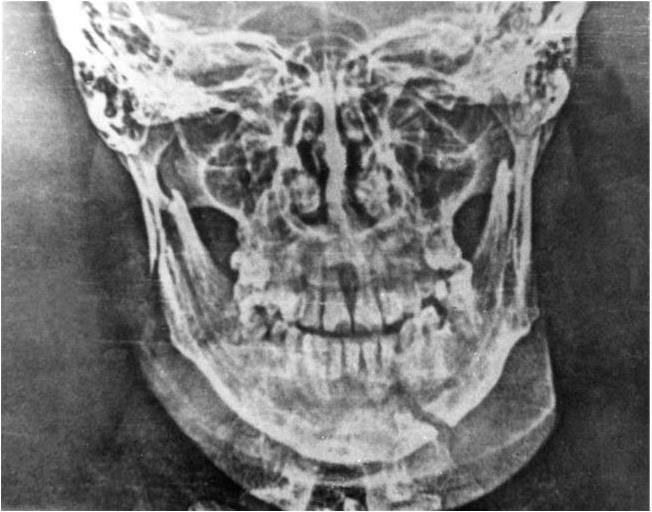

Для уточнения характера перелома, направления и степени смещения отломков, расположения щели перелома, а также соотношения между корнем зуба и щелью перелома необходимо провести рентгенологическое обследование. Прежде всего следует обязательно сделать обзорный снимок нижней челюсти (лобно-назальное предлежание больного к кассете), а для получения рентгенографической картины каждой половины челюсти – два боковых снимка. Для уточнения взаимоотношения зубов, расположенных в зоне перелома, со щелью перелома рентгенологическое обследование должно быть обязательно дополнено внутриротовым снимком.

Иногда для получения рентгеновского изображения височнонижнечелюстного сустава прибегают к укладкам по Шюллеру и Пордесу, а для того, чтобы получить представление о ходе щели перелома в подбородочном отделе, делают внутриротовой снимок: пленку помещают между зубами нижней и верхней челюсти, а тубус аппарата направляют на срединную часть подбородка снизу. Комплексное рентгенологическое обследование позволяет уточнить клинические данные о локализации перелома, направлении и степени смещения отломков (рис. 3).

При переломах мыщелкового отростка нижней челюсти для получения более точного представления о направлении и степени смещения малого отломка используют послойное исследование височно-нижнечелюстного сустава – томографию (Н.А.Рабухина). Томографические исследования (как во фронтальной, так и в сагиттальной плоскости) у больных с переломом различных отделов мыщелкового отростка, особенно в области шейки и суставной головки, подтверждают преимущества этого метода при подобных локализациях перелома (рис. 4).

Рис. 4. Томограмма нижней челюсти при переломе в области шейки справа и головки слева